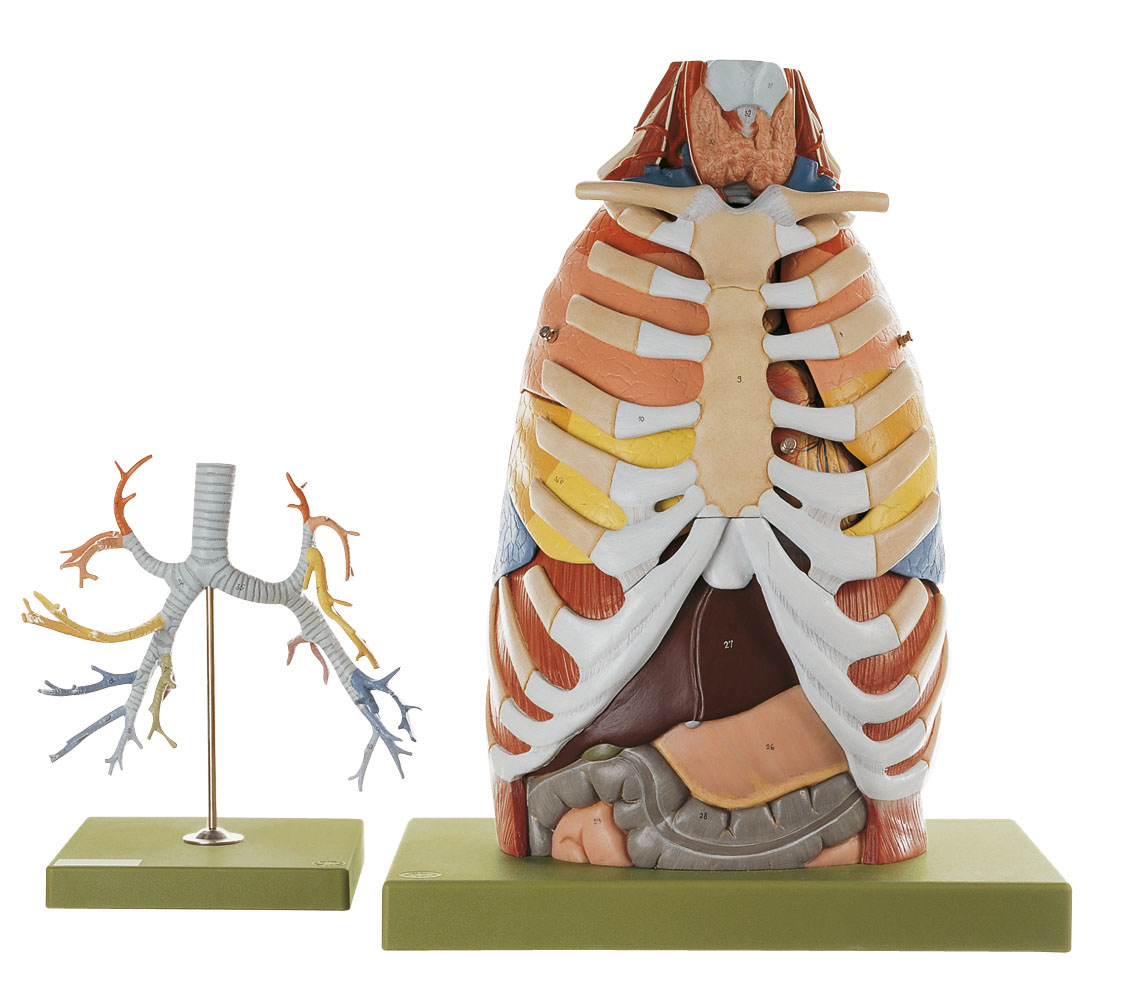

Lungs With Heart, Diaphragm and Larynx

- The model shows the viscera of the thorax

- Bifurcation of the trachea and oesophageal hiatus with aortic hiatus in the diaphragm is demonstrated